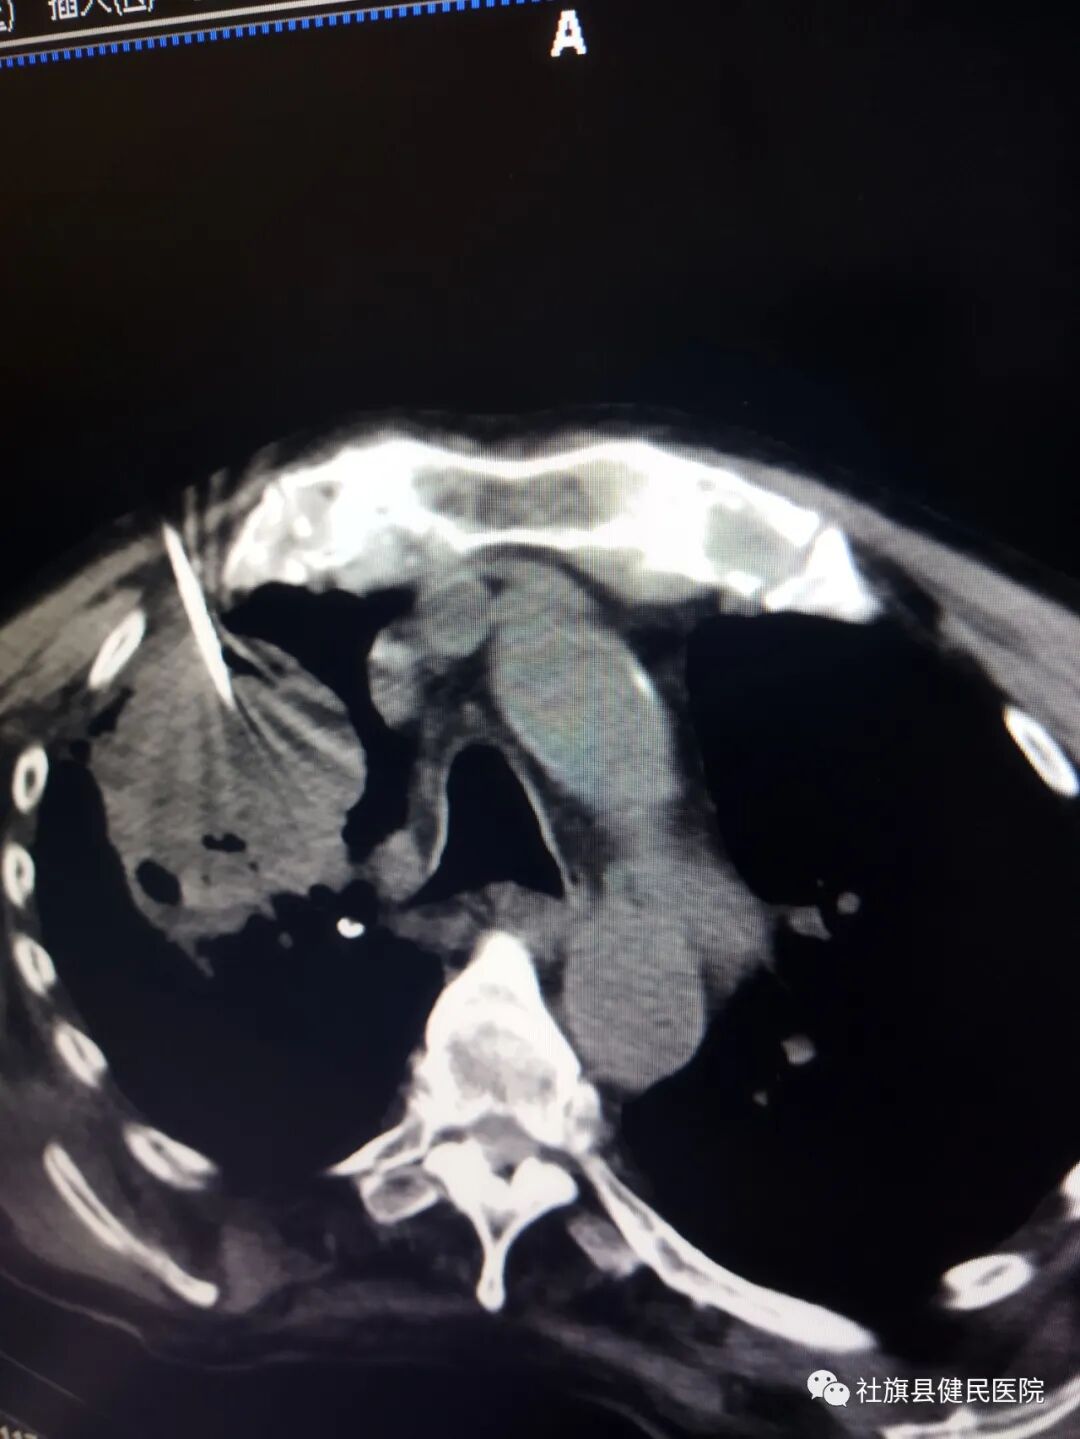

患者张某,男,84岁,来院前咳嗽、咳痰、气喘。三个月内体重下降近十公斤,辗转多家医院效果不佳,为求进一步诊治,在我院肿瘤科住院,住院期间经检查发现其右肺上叶占位,我院肿瘤科医师封冲,于2022年8月8日,在64排CT引导下,对病灶精准穿刺活检,诊断为右肺鳞癌。

精准的病理诊断,为临床治疗提供了可靠依据。精准的仪器、高超的技术,得到了患者及众亲友的一致好评。